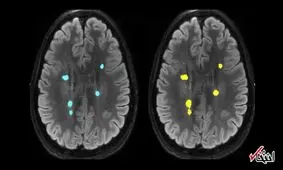

نایب رئیس انجمن پیشگیری و درمان چاقی ایران گفت: براساس تحقیقات انجام شده، هیپوکامپ سمت چپ مغز با مصرف نوشیدنیهای…